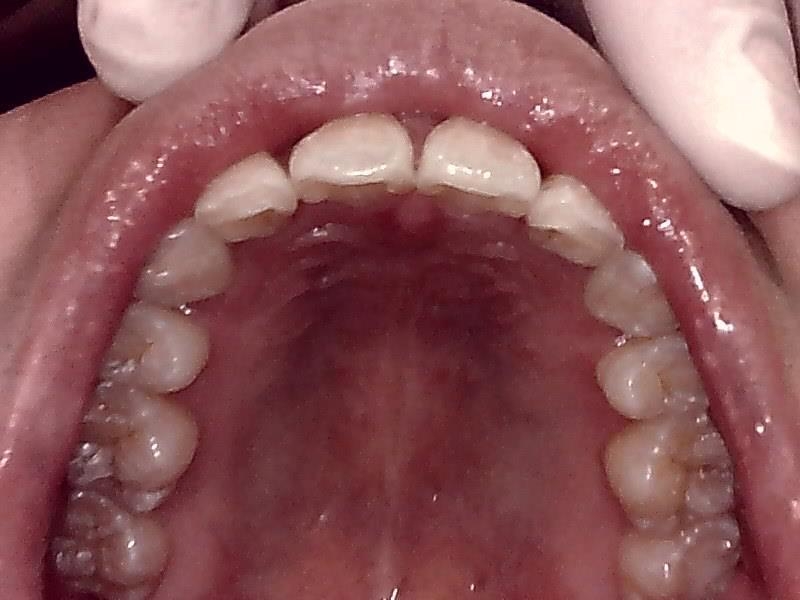

上顎咬合面観

下顎咬合面観